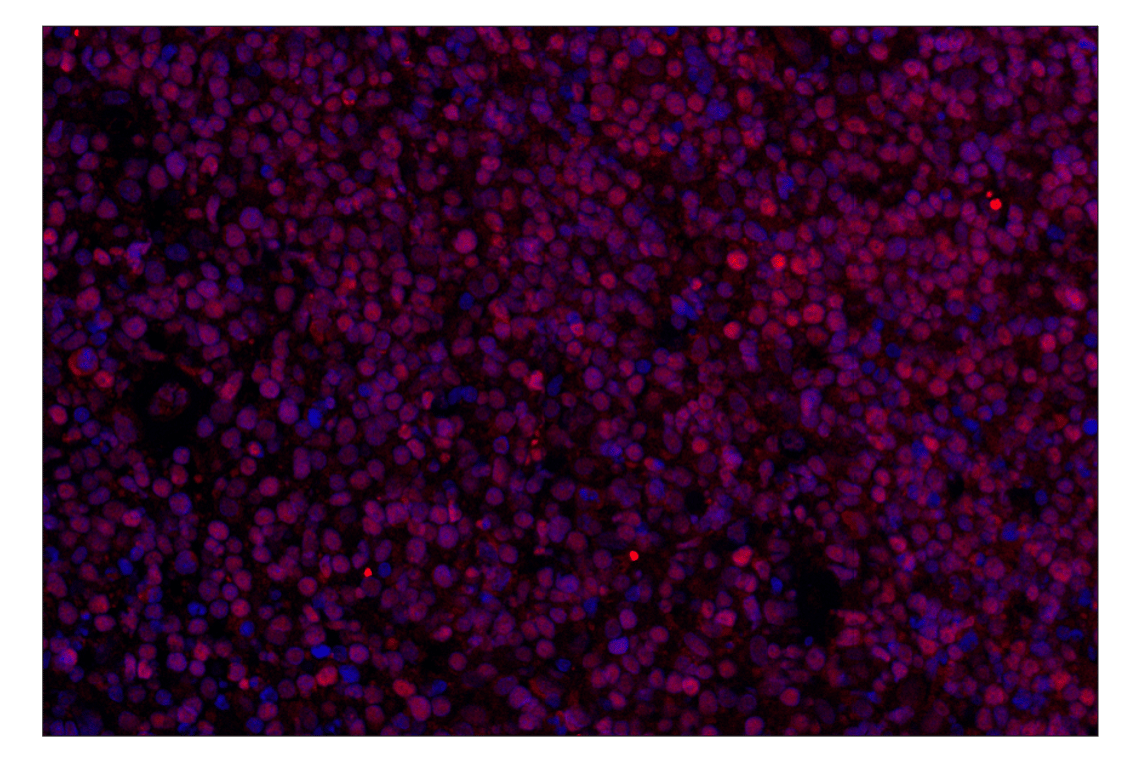

BCL6 (E5I8I) Rabbit Monoclonal Antibody (Alexa Fluor® 647 Conjugate) #62737

Immunohistochemistry (Paraffin) 1:50 - 1:200

BCL6 (E5I8I) Rabbit Monoclonal Antibody (Alexa Fluor® 647 Conjugate) recognizes endogenous levels of total BCL6 protein. This antibody conjugate is predicted to detect both known isoforms of human BCL6. Non-specific, non-nuclear staining was observed in human and mouse smooth muscle. Additional non-specific staining was observed in other mouse tissues.